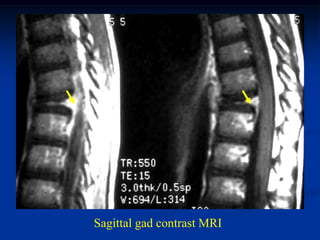

7 year male with EG T-11

Sagittal gad contrast MRI

Sagittal T-2 MRI showing protrusion into vertebral canal